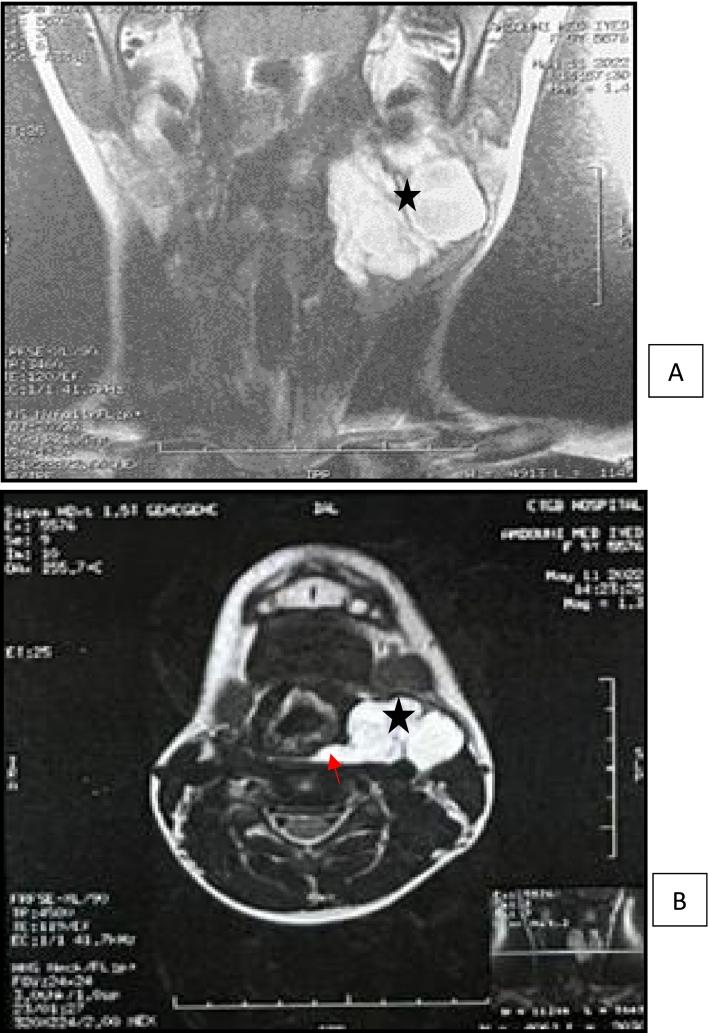

Cervical thymic cysts in children: A case report.

We report an observation of a cervical thymic cyst erroneously diagnosed preoperatively respectively as a cystic lymphangioma.

The diagnosis is generally rectified after surgery by identifying the specific histopathological findings of the thymic cyst. Treatment is surgical.

This diagnosis should be considered in front of any indolent lateral cervical mass.